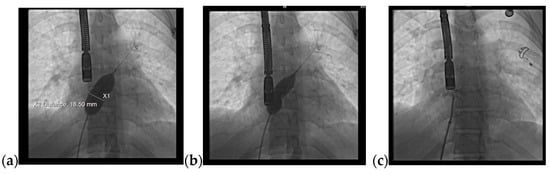

A 36-year-old non-smoker male patient, without cardiological follow-up and no cardio-active medication at home, presented with dyspnea, mild effort intolerance, and headache. Physical examination revealed peripheral cyanosis, body mass index (BMI) = 27.68 kg/m2, blood pressure (BP) = 115/70 mmHg, heart rate (HR) = 75 bpm, and unremarkable cardiac and pulmonary auscultation. The electrocardiogram showed sinus rhythm, HR = 75 bpm, rSR’ pattern in precordial leads V1 or V2 (Figure 1a). The chest radiography revealed a normal heart size with hilar bilateral enlargement and increased vascular density in the upper half of the hilum (Figure 1b).

Figure 1.

(a) 12-lead ECG revealed sinus rhythm and rSR’ pattern in precordial leads V1 or V2; (b) Postero-anterior chest view radiography showed hilar bilateral enlargement and increased vascular density in the upper half of the hilum. Abbreviations: ECG—electrocardiogram.